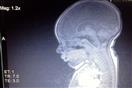

حالة نادرة.. تفاصيل حياة طفلة مولودة بنصف مخ فقط (صور)

قبل 6 أشهر وُلدت الطفلة "ليلي ويذرال" بنصف دماغ فقط، فاعتقد الأطباء أنها ستموت بعد عدة أشهر من ولادتها، لكن ما حدث عكس ذلك.

كانت "ليلي" تبدو طبيعية بعد الولادة لكن تم تشخيصها بوجود جزء مفقود من الدماغ بعد إجراء فحوصات على المخ، بحسب موقع جريدة "Daily Mail" البريطانية.

تحدث هذه الحالة عندما تكون أجزاء كبيرة من الأجزاء الصلبة من نصف الدماغ مفقودة ويتم استبدالها بالسوائل، وقيل للوالدين أن ابنتهما عمياء وصماء ولن تعيش طويلًا بعد الولادة.

وتقول الأم إن "ليلي" لم تكن قادرة على الرؤية أو فتح عينيها لمدة أسبوع بعد الولادة، "كما لن أسمع صراخها لمدة أسبوعين، وقال الأطباء إن "ليلي" كانت صماء وعمياء، لكننا لم نكتشف سبب لك إلا بعد شهر كامل، بعد إجراء فحص على المخ".

وبينت الأشعة والفحوصات أن "ليلي" لا يزال لديها جذع الدماغ المسئول عن التنفس والوظائف الحيوية بالإضافة إلى المخيخ المسئول عن حركات العضلات.

ويحتوي الجزء المفقود من مخ "ليلي" على الفص الجبهي والفص الصدغي والفص الجداري والفص قذالي، وكلها تتحكم في قائمة ضخمة من العواطف والإحساس باللمس والذاكرة والكلام وحركات الجسم، ويمكن أن يسبب هذا مشكلات في الرؤية والسمع بالإضافة إلى الإعاقة الذهنية والجسدية والنوبات وتصلب العضلات وضعفها.